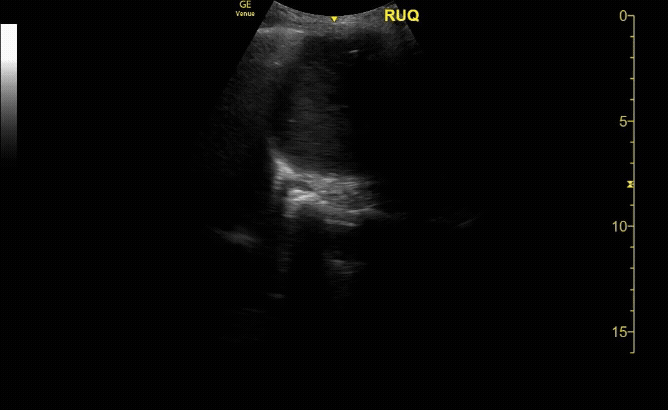

RUQ view showing large peural Effusion as well as ascites.

c/o Derek Hilgers, MD